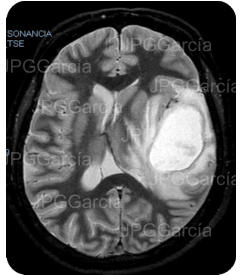

Resonancia magnética de cráneo en secuencias T1 y T2 que muestran una lesión ocupante de espacio de localización fronto temporal izquierda que ejerce efecto de masa aunado a edema perilesional

Secuencia de resonancia craneal DW1 y STIR que muestran diferentes intensidades dentro de la lesión descrita que ejerce efecto de vector contra estructuras cerebrales